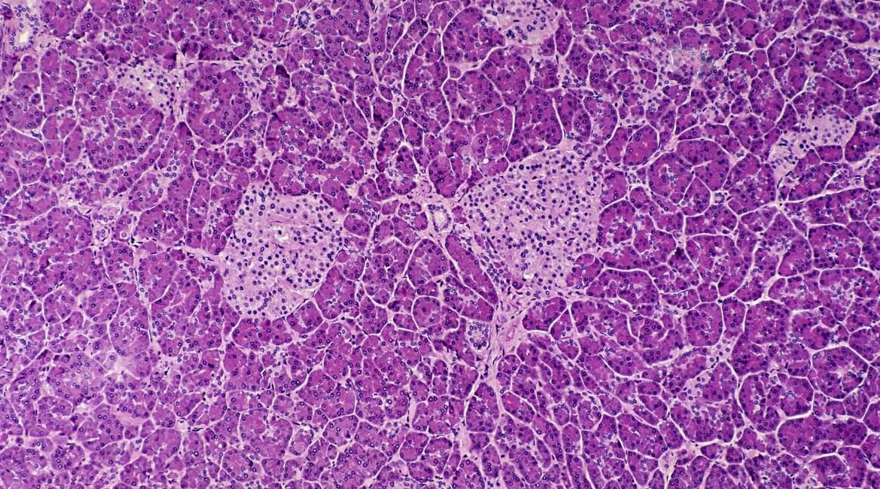

دیابت نوع ۱ بیماری خود ایمنی است که در آن سلول‌های بتا تولیدکننده انسولین در لوزالمعده، به طور انتخابی از بین می‌روند‌ و مبتلایان به تزریق روزانه انسولین نیاز دارند. از طرفی تنها درمان مؤثر، پیوند جزایر پانکراس است که با وجود نتایج خوب برای افراد مبتلا به دیابت، به اهداکنندگان عضو وابسته است؛ بنابراین استفاده‌ی گسترده از آن محدود شده است. سلول‌های پیش‌ساز پانکراس، سلول‌های بنیادی هستند که توانایی تمایز به سلول‌های مختلف پانکراس، از جمله سلول‌های بتا را دارند. برنامه‌ریزی مجدد این سلول‌های بنیادی به سلول‌های بتا تولیدکننده انسولین و پیوند مجدد آن‌ها در لوزالمعده، قبلاً به‌عنوان یک درمان جایگزین برای دیابت نوع ۱ پیشنهاد شده بود اما بحث‌برانگیز باقی مانده است.

برای بررسی این روش، این تیم سلول‌های بنیادی پانکراس را از یک اهداکننده دیابتی نوع ۱و همچنین از دو اهداکننده غیردیابتی، جمع‌آوری کرده و آن‌ها را با GSK126 درمان کردند. GSK126 فعالیت یک آنزیم کلیدی به نام  EZH2 متیل ترانسفراز را مهار می‌کند. این آنزیم بیان ژن‌هایی را مهار می‌کند که منجر به تمایز پیش‌ساز به سلول‌های بتا می‌شوند.